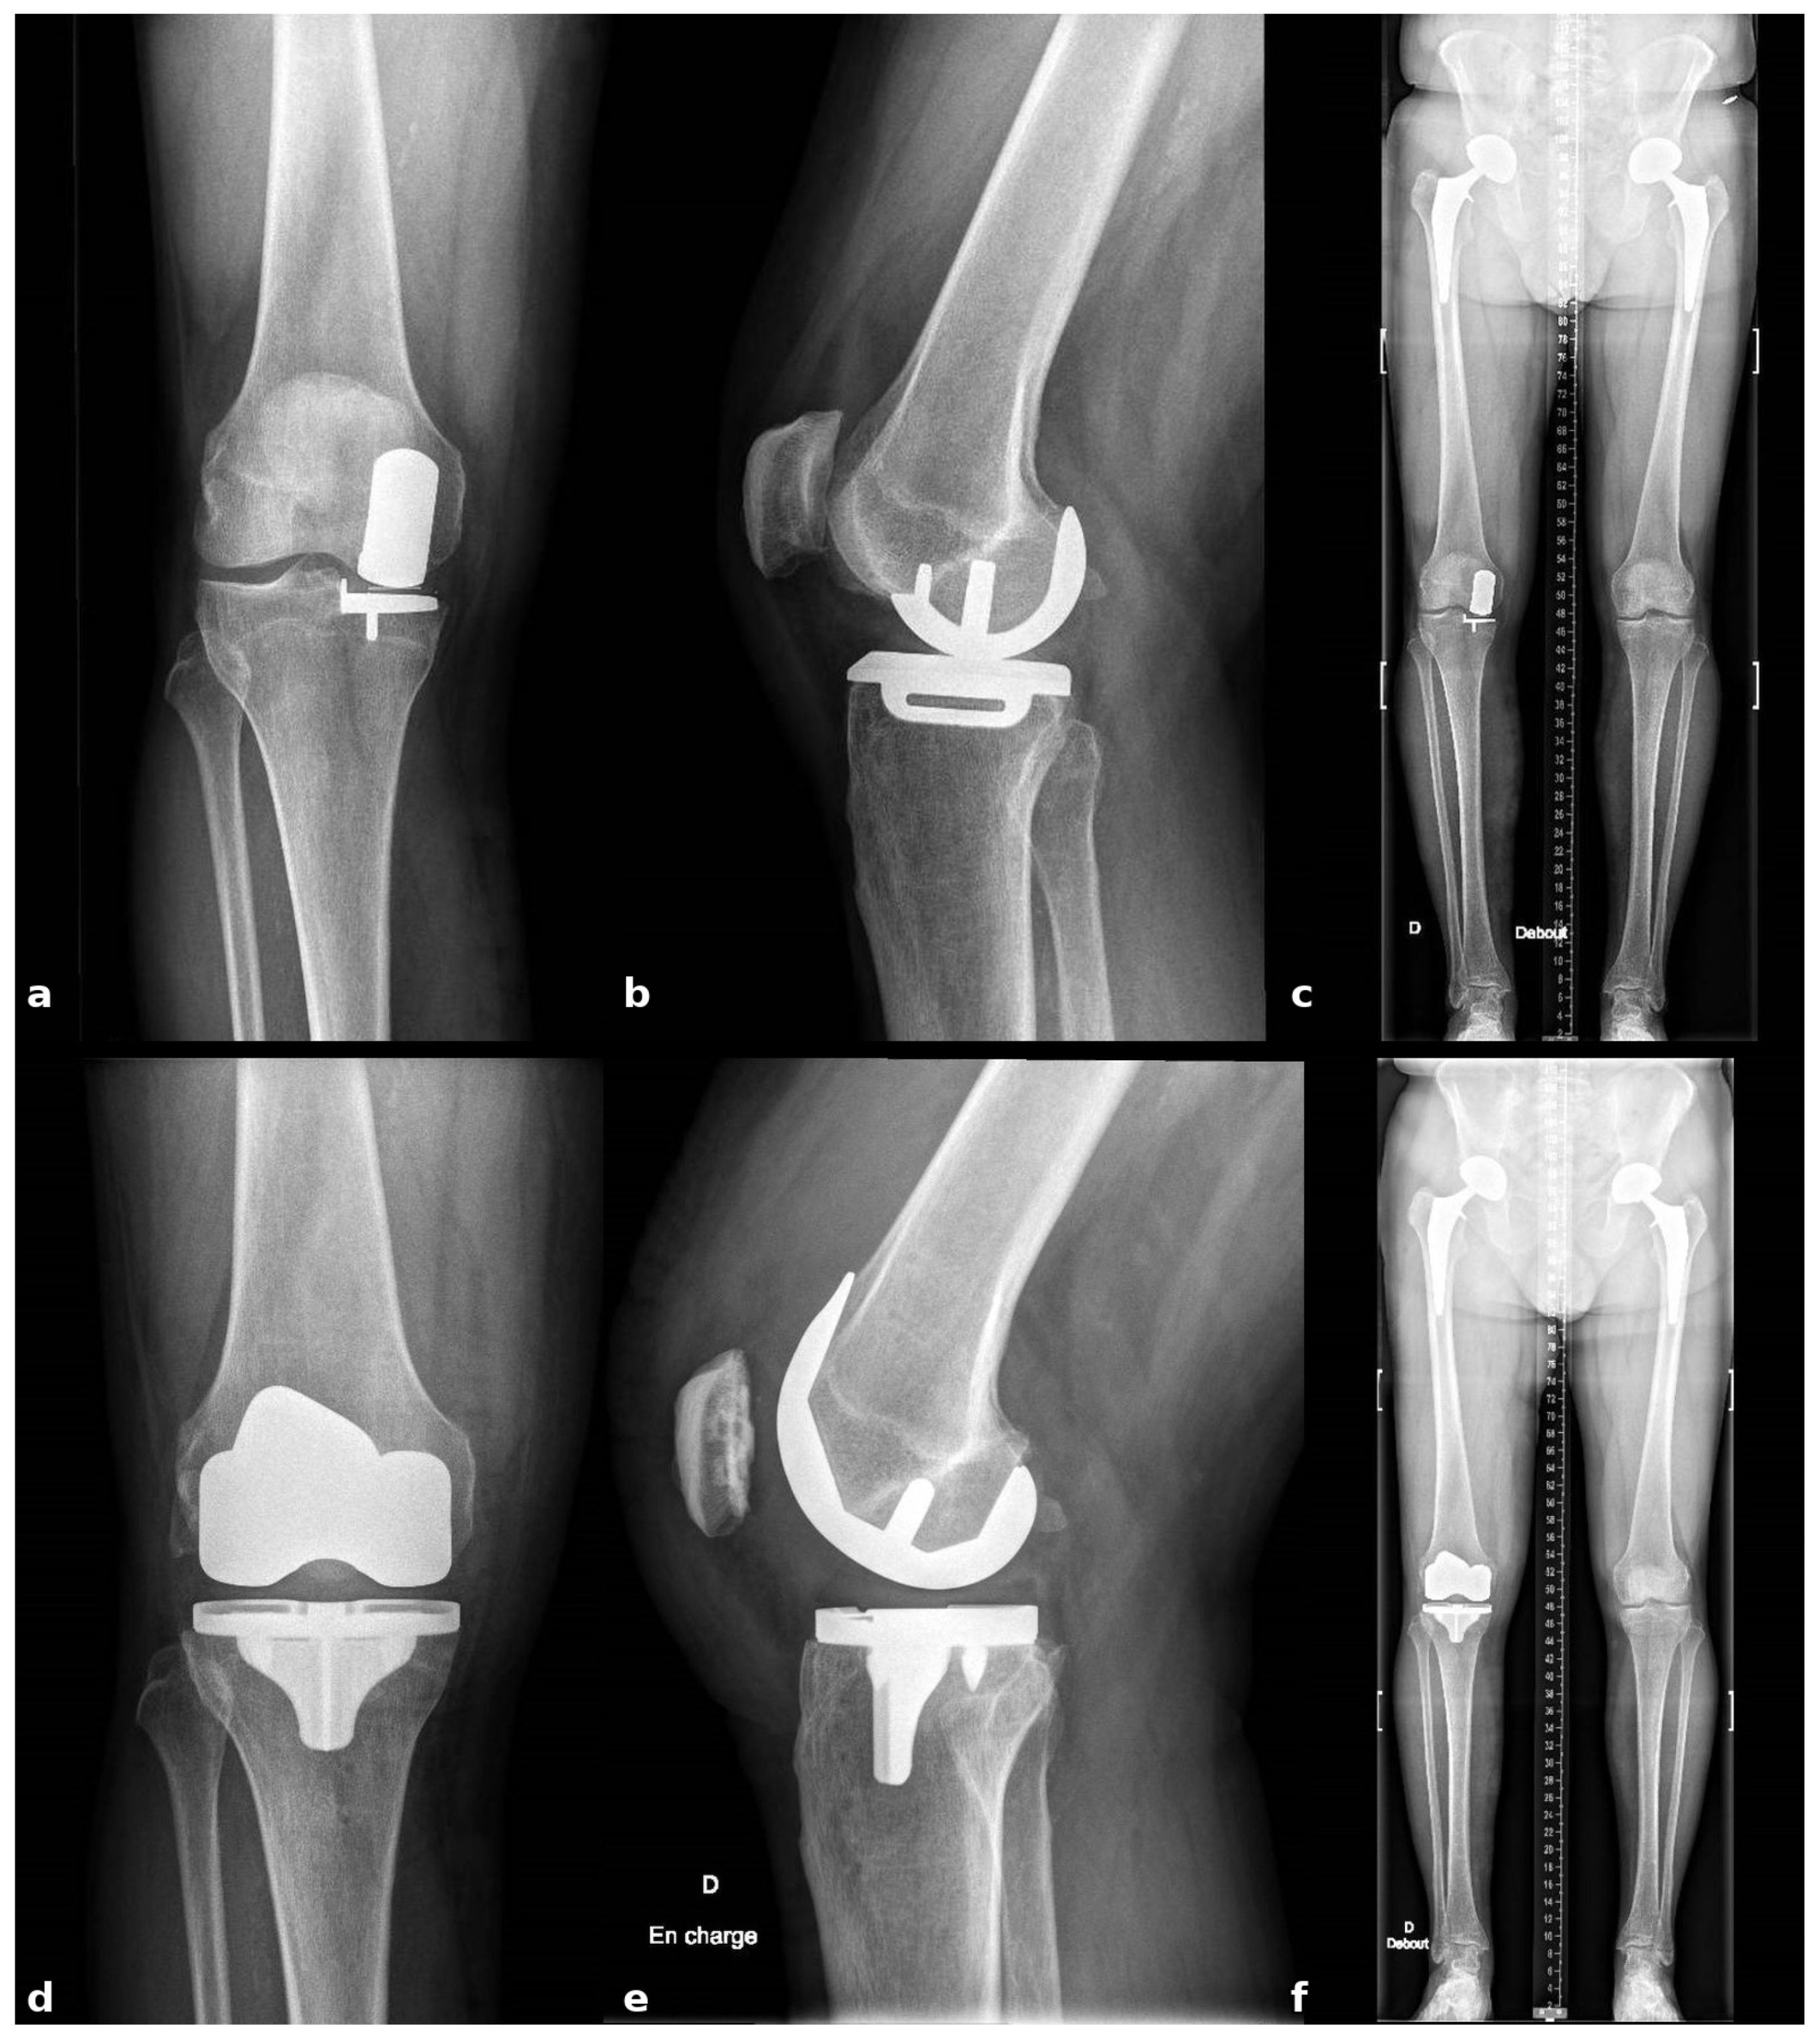

2.4. Intraoperative Functional Alignment and Ligament Balance Assessment

With the UKA components in place, an initial intraoperative functional alignment assessment is performed (Figure 3). The polyethylene insert is reinserted to enable a dynamic evaluation of ligament balance in both flexion and extension, providing essential data for potential plan adjustments. After registration and verification of reference points, this assessment is repeated through the full range of motion, allowing real-time adaptation to refine the 3D plan.

Figure 3.

Intraoperative ligament balance assessment after registration. The polyethylene insert is reinserted prior to implant removal to evaluate dynamic ligament balancing through flexion and extension.

Varus–valgus stress tests are applied at multiple flexion angles to assess ligament balance. The target is 1–2 mm of controlled laxity with symmetric medial and lateral gaps in extension and at 90° of flexion. The medial–lateral side-to-side difference should be ≤1 mm to maintain optimal soft-tissue tension and avoid mid-flexion instability.

Within a functional-alignment strategy, balance is restored by adjusting implant positioning and resection targets rather than by performing ligament or soft-tissue releases. This bone-preserving functional-alignment strategy maintains the native joint line and creates optimal conditions for accurate, conservative implantation.